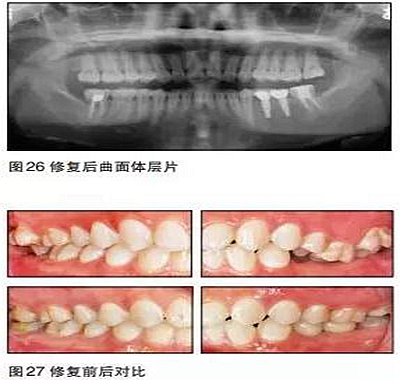

小結(jié)

在本病例中,患者的主觀愿望是想通過種植來修復(fù)缺失牙??趦?nèi)檢查及口腔曲面體層片顯示患者缺牙區(qū)的骨質(zhì)良好,骨量充分,但咬合情況非常復(fù)雜。如果不先通過正畸治療來改善咬合而直接進(jìn)行種植手術(shù),那么后期的修復(fù)將異常困難。

本病例的難點在于如何創(chuàng)造適合種植的咬合條件。17、47、27、37正鎖,25、26過長。傳統(tǒng)矯治正鎖時往往采用上下頜交互牽引的方式,但這種方法會導(dǎo)致磨牙不必要的伸長,且有明顯的疼痛感。本病例采用種植支抗釘技術(shù),在矯正17、47、27、37

正鎖的同時壓低相應(yīng)牙齒,在較短的時間內(nèi)完成了后牙鎖及伸長牙的矯正,且患者感覺較為舒適。

35、36種植時采用骨水平的NobelActive植體;由于植體位置比較理想,修復(fù)體采用螺絲固位的氧化鋯基臺一體冠,便于今后牙冠及種植體的維護(hù)。最終種植修復(fù)完成后在咬合、美觀、牙齦乳頭充盈等方面都取得了滿意的效果。